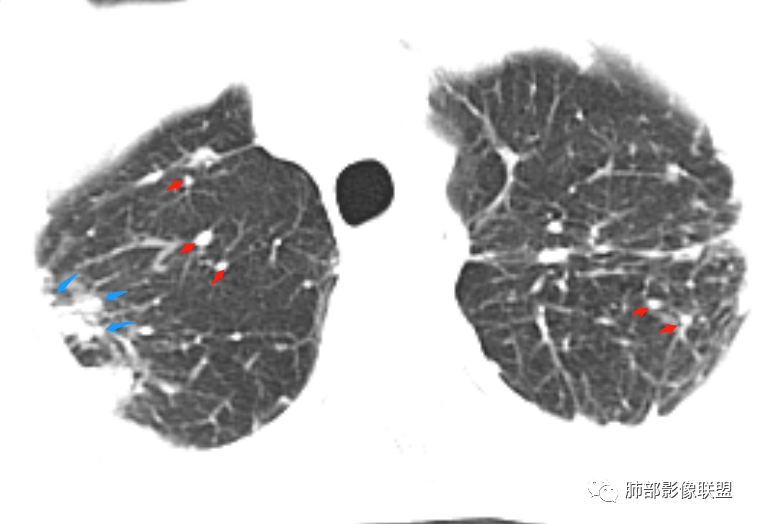

本例肺结核的影像征象:

1、树芽征

2、多发结节,卫星灶

3、小叶间质增厚,有索条影

4、反晕征

5、纵隔淋巴结肿大

临床及影像:

1.双肺片状影、大小不等斑片影、结节影、树芽等,病灶密度偏高多钙化。

2.病灶上肺为主,胸膜下分布为主。双肺病灶明显不对称,右肺块状影较大。

3.纤维条索影广泛杂乱、牵拉,横向分布为主,这点给人也印象很深!

4.纵隔轻度右移。双肺门纵隔淋巴结增大钙化。